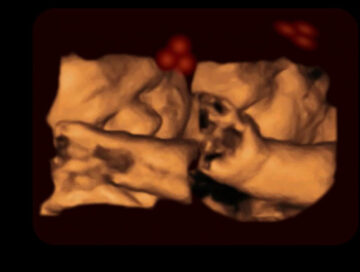

Dispositivo de ultrasonido 4D

Hasta el momento, otros estudios no habían podido observar las reacciones del feto frente a estímulos concretos, debido a cuestiones técnicas. Ahora los cientíticos han utilizado un dispositivo de ultrasonido 4D de alta calidad para estudiar su comportamiento.

Para realizar este estudio, los investigadores han analizado las repuestas de 39 fetos ante figuras lumínicas con formas de caras, proyectadas con distintas orientaciones. Las luces emitidas las movían a través de sus campos de visión, mientras observaban con el ultrasonido 4D sus reacciones.

Las películas obtenidas muestran que los bebes se sentían más atraídos por los rostros ‘normales’, que por los invertidos. Con estos resultados, los autores sugieren que los bebes adquieren antes del nacimiento la capacidad para reconocer caras. Además, han comprobado que la luz exterior puede atravesar los tejidos humanos y llegar al útero.